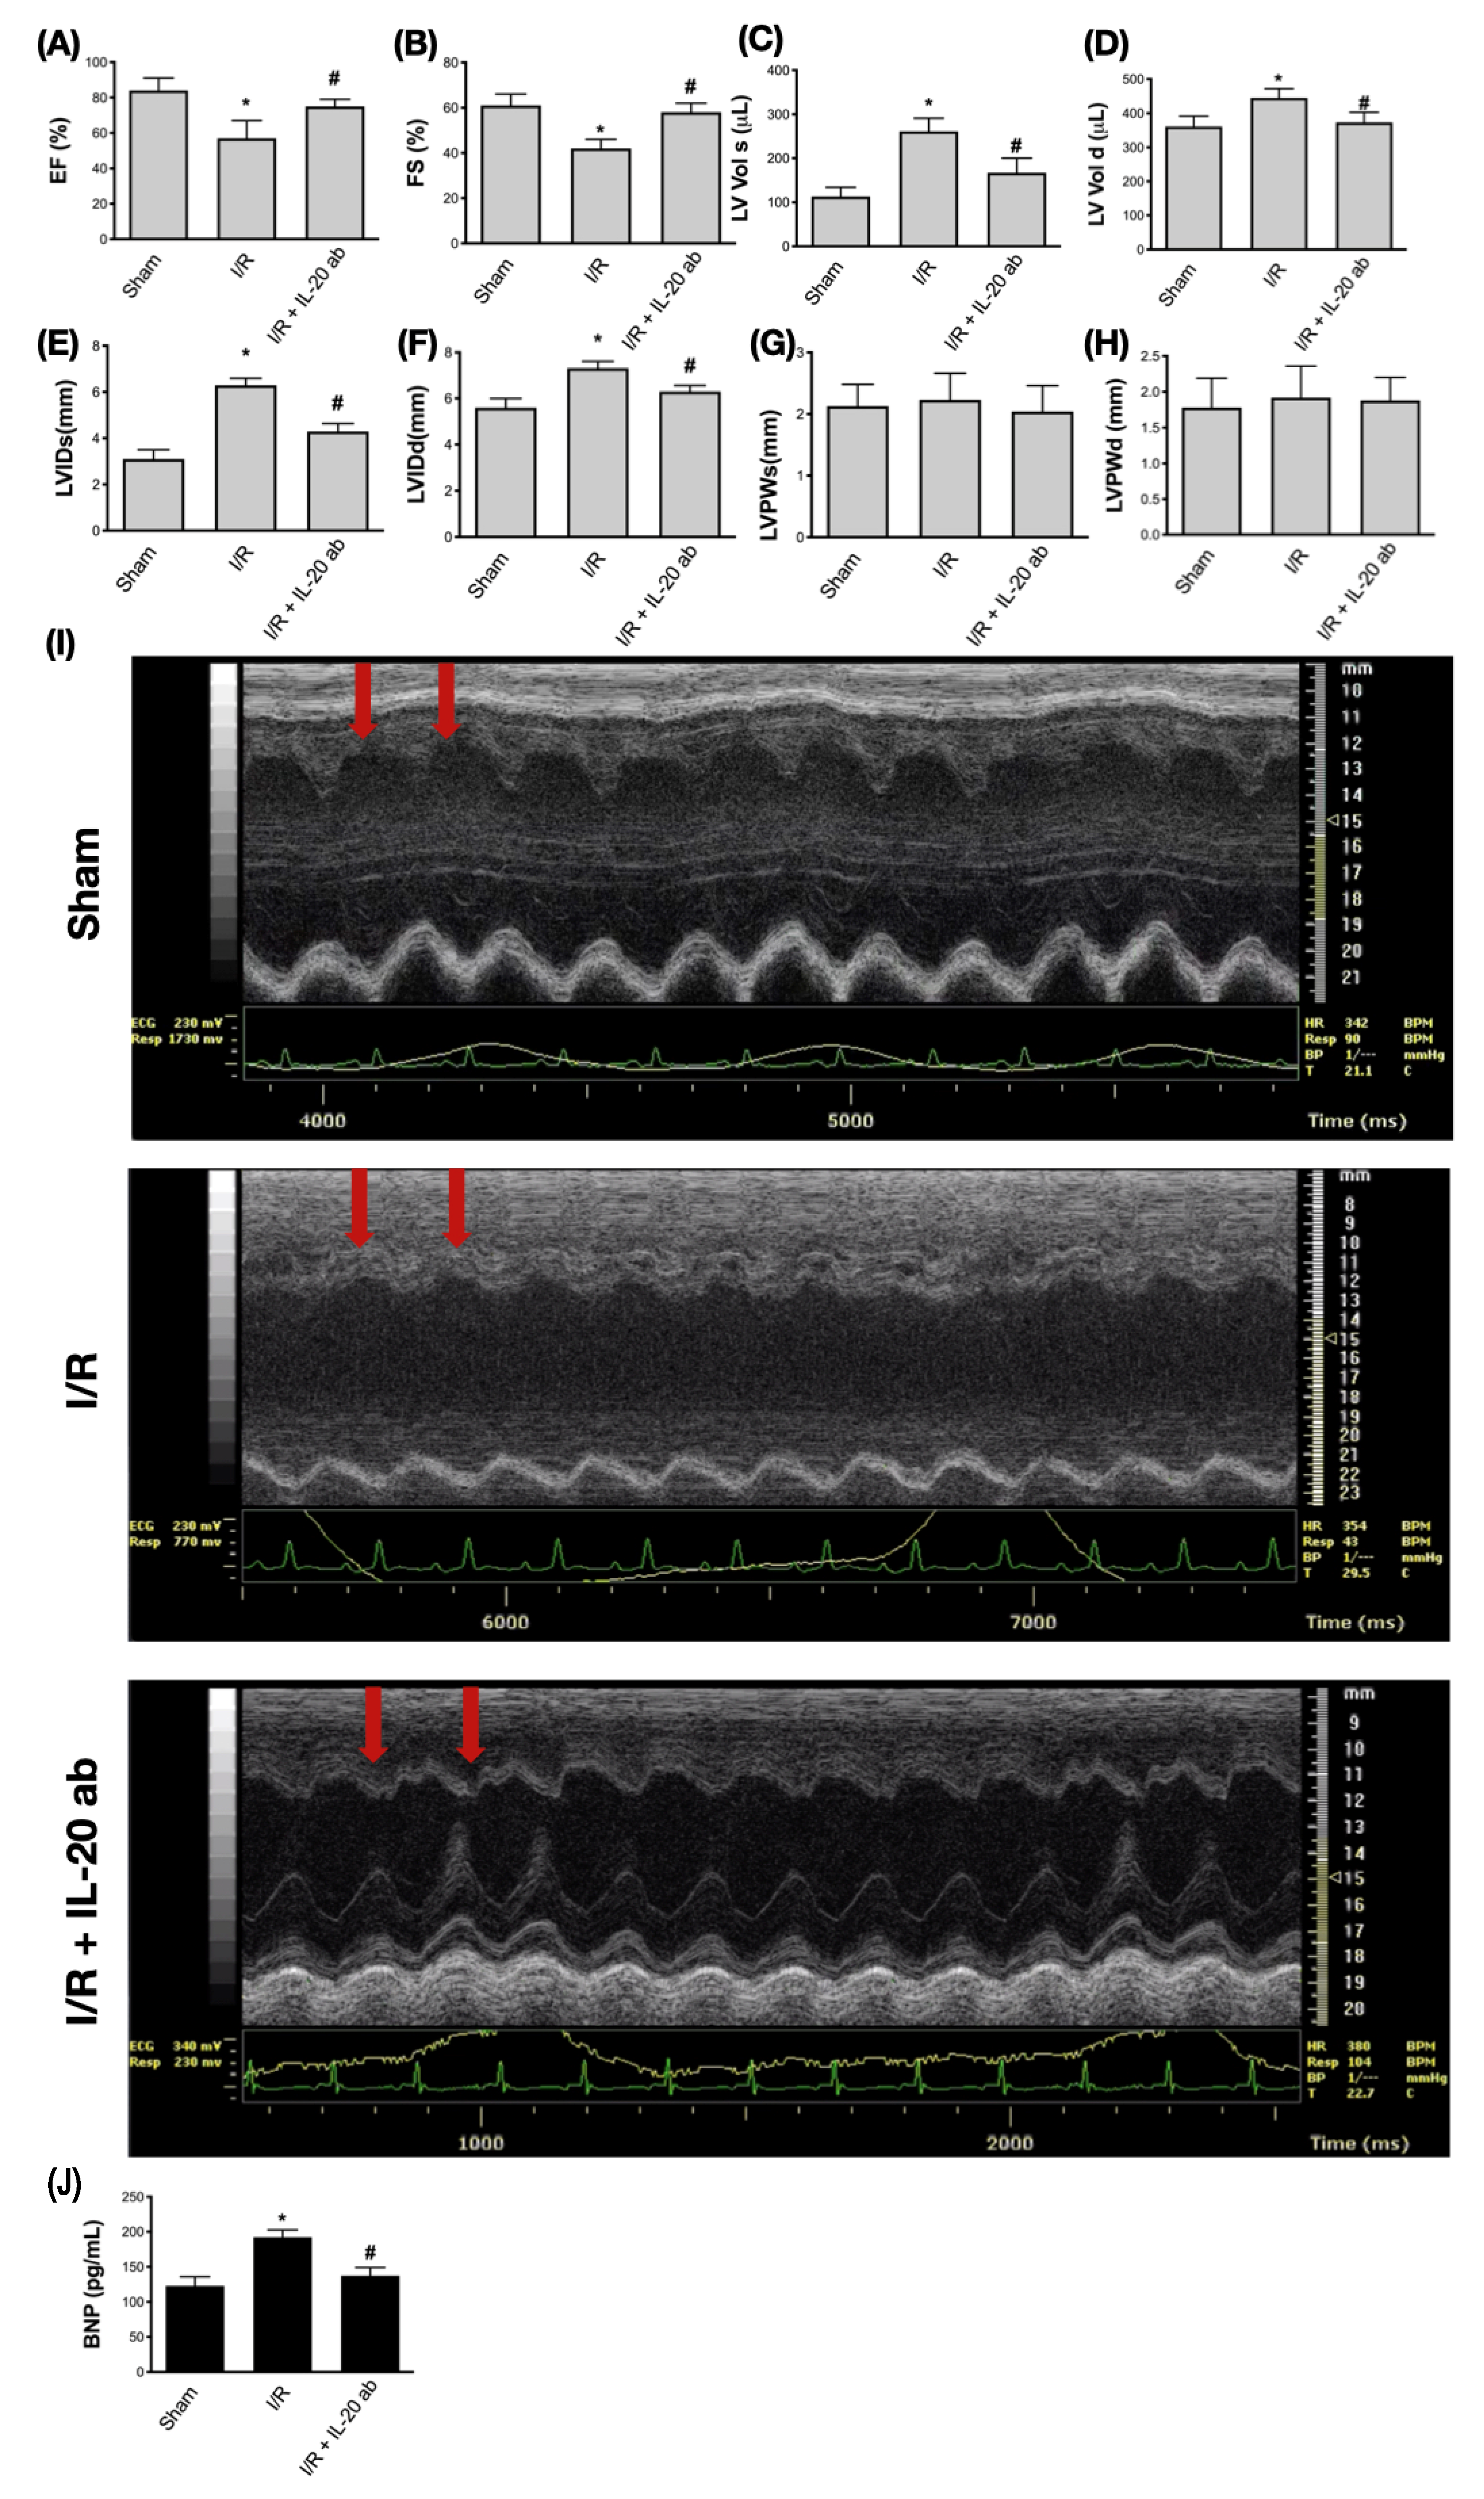

3.6. Treatment with Anti-IL-20 Antibody Reduces Myocardial Infarction-Caused Heart Function Impairment

Next, to evaluate the therapeutic effect of IL-20 antibody in myocardial infarction, we used echocardiography to monitor cardiac function. The left ventricular ejection fraction (Figure 6A) and fractional shortening (Figure 6B) were decreased in the setting of I/R, indicating that the contractive function of left ventricle was reduced by myocardial injury. Treatment with IL-20 antibody could improve the left ventricular contractive function in terms of ejection fraction (Figure 6A) and fractional shortening (Figure 6B). Myocardial injury caused dilatation of left ventricle, represented by the increased volume of left ventricle at either end systole (Figure 6C) or end diastole (Figure 6D) as well as increased internal dimension of left ventricle at both end systole (Figure 6E) and end diastole (Figure 6F). Injection of IL-20 antibody could reverse the effects of I/R injury on chamber dilatation of the left ventricle (Figure 6C–F). There was no significant difference in the thickness of the left ventricular posterior wall at end systole (Figure 6G) and end diastole (Figure 6H) among sham group, I/R group, and I/R plus IL-20 antibody treatment group, suggesting that the ligation of LAD coronary artery was successful without interfering other coronary artery flow. The function of the anterior wall of left ventricle was impaired whereas the posterior wall was unaffected. In addition, compared to control animals (Figure 6I, upper panel), the motion of the anterior wall of left ventricle (red arrows) in M-mode echocardiography was decreased under I/R injury (Figure 6I, middle panel). Treatment with IL-20 antibody improved the impaired motion of anterior wall (Figure 6I, lower panel). Impaired left ventricular contraction and dilatation of left ventricle are important features of CHF. Our data imply that IL-20 antibody has the ability to protect heart function from I/R injury. This finding was supported by plasma BNP concentration examination. The increase in plasma levels of BNP after I/R insult was attenuated by IL-20 antibody injection (Figure 6J). Moreover, in compliance with our previous results, we further proved that the concentrations of LDH and CK-MB in plasma were increased after I/R intervention. These two factors are commonly used to determine the severity of myocardial injury [35]. As expected, we confirmed that IL-20 antibody injection at reperfusion is an effective way to mitigate the I/R-induced myocardial injury (Figure 7A,B).

Figure 6.

Examination of cardiac function using echocardiography. The parameters of the left ventricular function were measured using M-mode echocardiography. The ejection fraction (EF) (A) and fractional shortening (FS) (B) of left ventricle were measured to determine the left ventricular contraction ability. The volume of the left ventricle at end systole (C) and at end diastole (D), the internal dimension of left ventricle at end systole (E) and at end diastole (F), as well as the left ventricular posterior wall thickness at end systole (G) and at end diastole (H) were measured to determine the dilatation of left ventricle. Representative images of M-mode echocardiography were shown to demonstrate the rescue of ischemia/reperfusion (I/R)-induced cardiac dysfunction by interleukin (IL)-20 antibody treatment. Red arrows indicate the anterior wall of left ventricle (I). The concentrations of plasma B-type natriuretic peptide (BNP) were checked to determine the degree of cardiac dysfunction (J). The data were presented as the mean ± standard deviation of six animals in each group (* indicating p < 0.05 compared to the sham group; # indicating p < 0.05 compared to the I/R group).